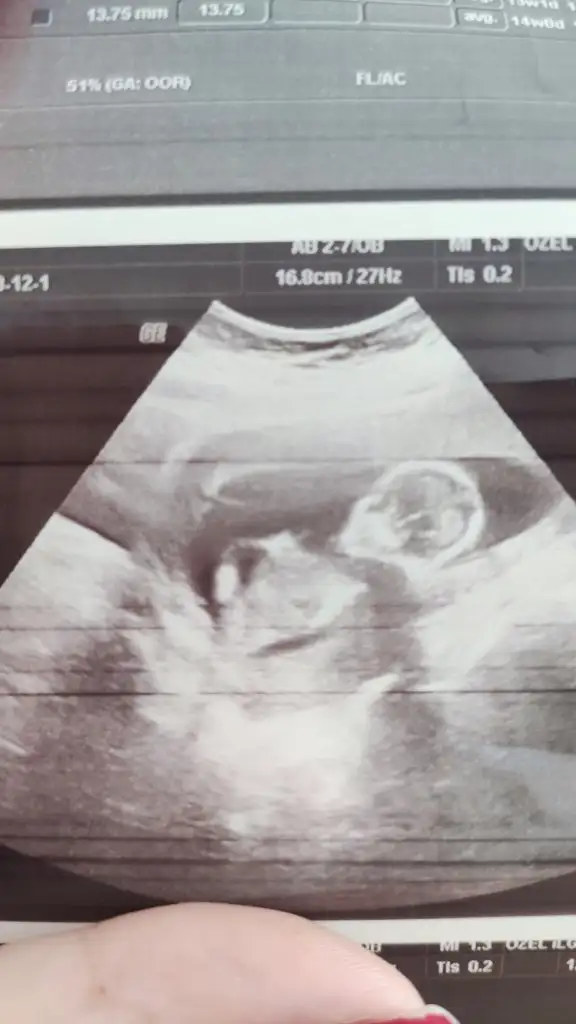

5 ve 14. haftaya kadar olan ultrason fotolarınızı paylaşın. Vajinadan mı yoksa karından mı çekildiğini ve kaç haftalık olduğunu da mutlaka belirtin.